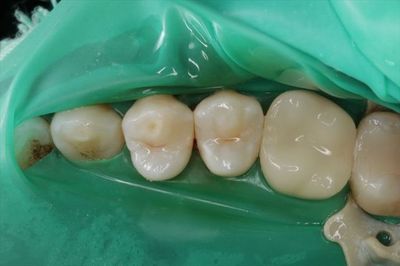

咬合調整と仕上げ研磨を終えました。